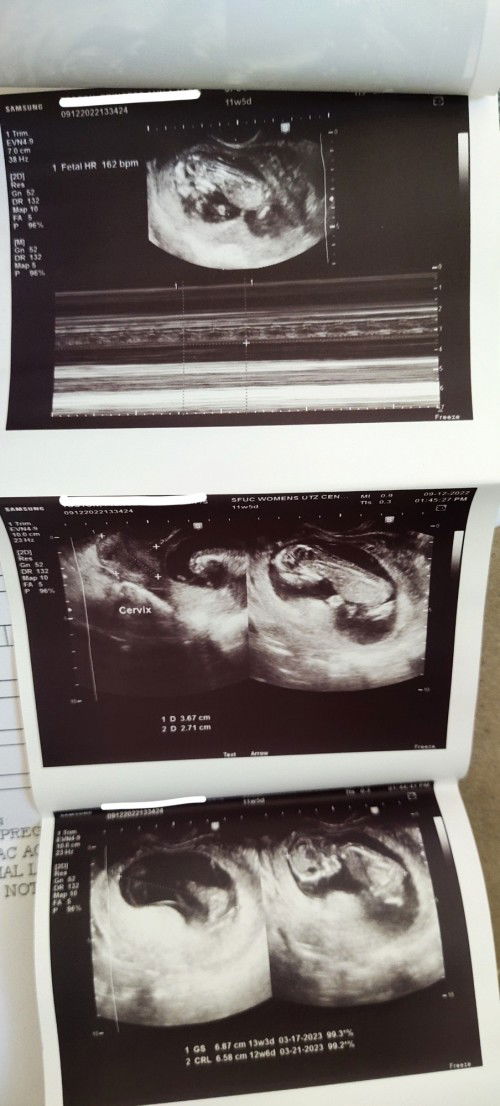

13 weeks and 2 days pregnant

Hello ask ko lang po kung malambot po ba or medyo matigas ang nararamdaman kapag kinakapa sa bandang puson? Di ko sure kung nagkakabump ba tyan ko kasi malaki talaga puson ko before pregnancy nanenega ako naiisip ko kasing wala si baby sa loob pero nagpaultrasound ako 11weeks and 5days mukha naman syang healthy. #firsttimemom